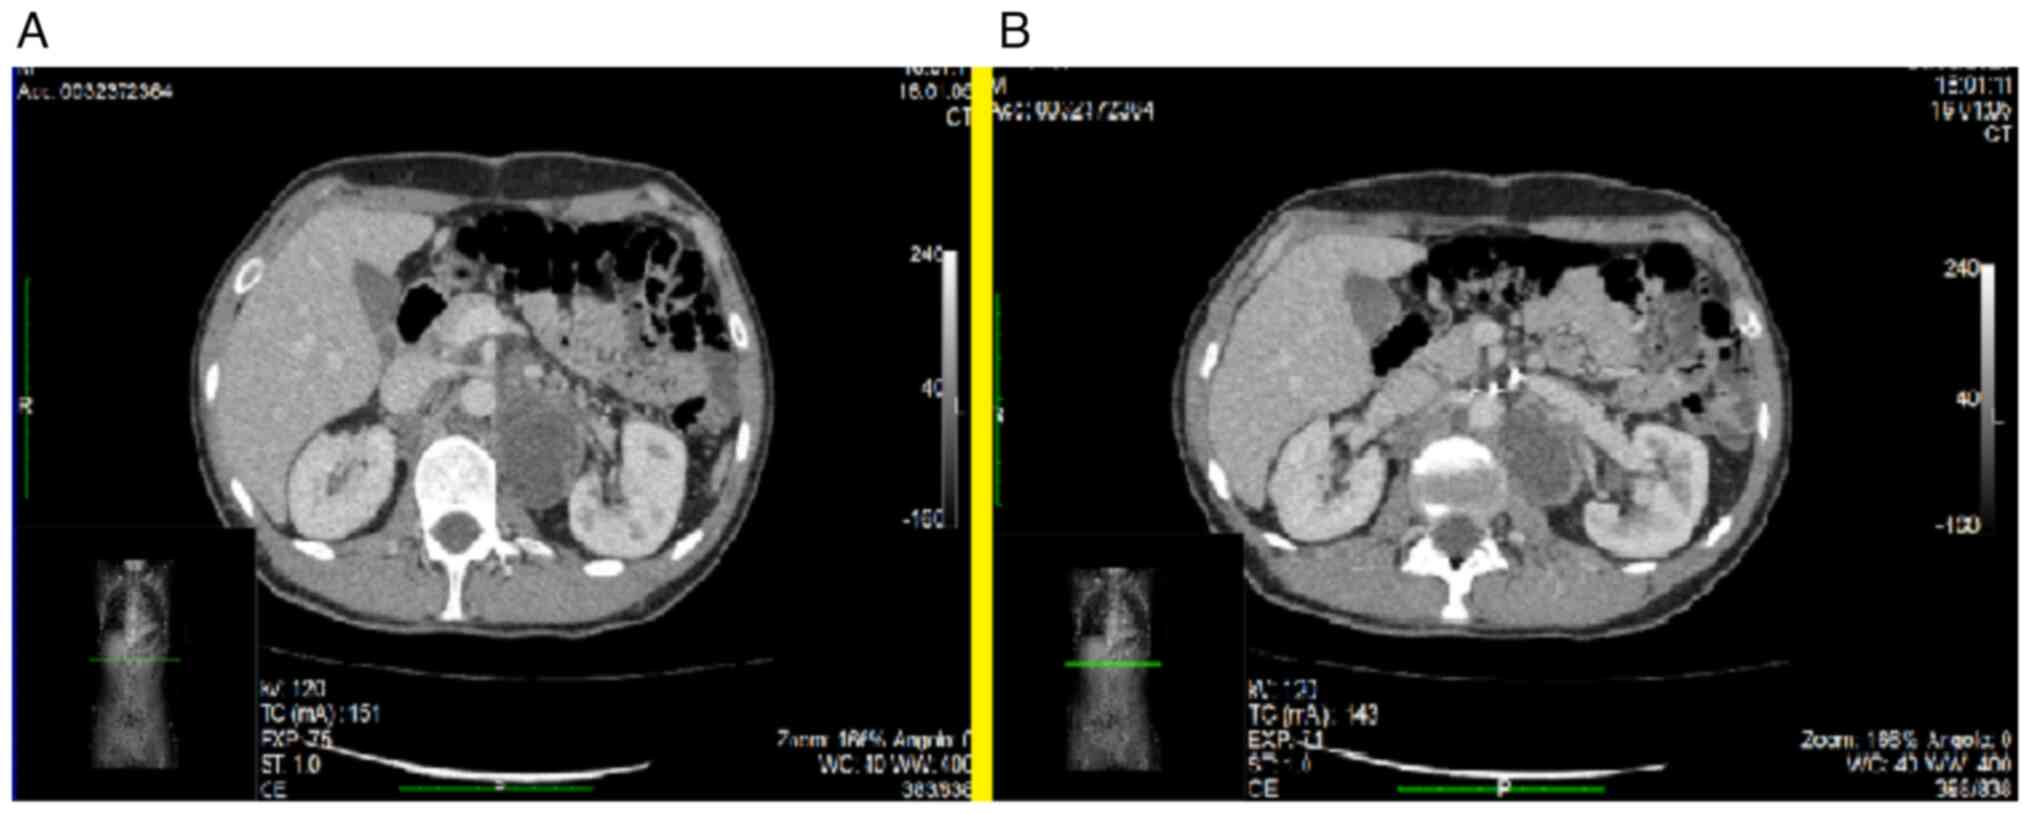

A post-operative CT scan was repeated 2 months later, which revealed no abdominal residual masses. At 3 months after surgery, the ureteral stents were removed. Subsequently, the patient was admitted to the Thoracic Surgery Unit for an open removal of thymus, subcarinal lymph node extending up to the arc of the azygos, left latero-cervical lymph node and neoformation of the anterior mediastinum. The thymic parenchyma resulted in partial adipose involution, but the other three samples were affected by germinal neoplasia, consisting of both cystic and solid areas, with elements of derivation of the three embryonic sheets. Respiratory, gastro-enteric and Mullerian epithelium were identified. There were no structures referable to the lymph node. At 6 months' post-operation, a control CT scan revealed a hypodense formation in the anterior para-aortic site, strictly adjacent to the aortic arch. Furthermore, the retroperitoneum was affected by tumor recurrence. In particular, the following tumors were documented: in the lumbar aortic left region, long and close to the common iliac and external left vascular axis (Figs. 2A and B and 3B); and in the retrocaval region that compressed and displaced the venous vascular lumen anteriorly (Fig. 3A).

Figure 2

Follow-up performed with imaging techniques after the first surgery. This control CT scan revealed tumor recurrence of the retroperitoneum: (A) In the lumbar aortic left region (where a mass occupying space is visible between the aorta and the vascular peduncle of the left kidney), (B) long and close to the common iliac and external left vascular axis (since the mass extends to the bifurcation of the aorta into the iliac arteries).